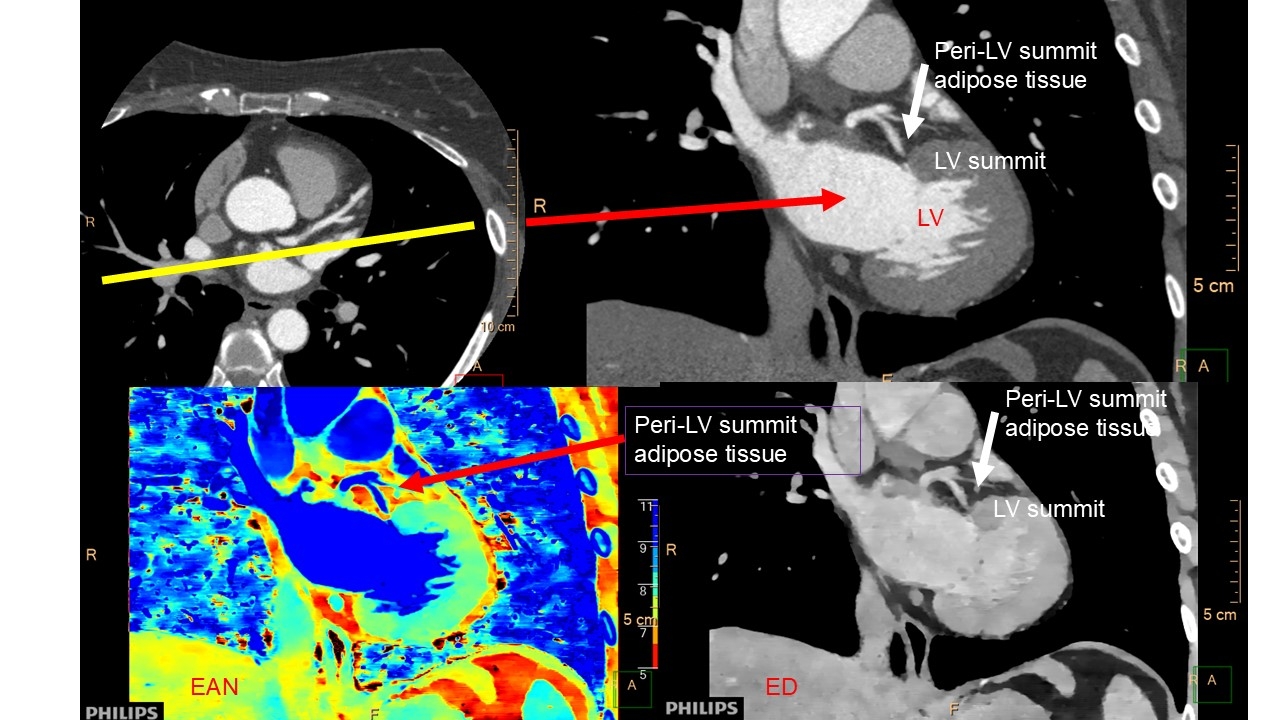

Hypothesis: Using effective atomic numbers (EANs) and electron density (ED) measurements determined by spectral CT as new parameters, the focal characteristics of peri-LVS adipose tissue are useful in predicting the occurrence of VAs.

Methods: This is a retrospective analysis of 11 patients (7 males; mean age, 69 ± 12 years; plasma brain natriuretic peptide, 166±145 pg/mL) with atrial fibrillation who were scheduled for pulmonary vein isolation. They underwent dual energy CT (7500, Philips) and routine late phase CT contrast acquisition to evaluate left atrial thrombi and 24-hour Holter ECG. From non-contrast and early- and late-phase contrast data, CT attenuation, EANs and EDs (%ED relative to water) of peri-LVS adipose tissue were determined and compared to those of peri-coronary (proximal portion of right coronary arteries) adipose tissue as a reference on CT images.

Results: Comparing the two sites, on non-contrast CT images, mean CT attenuations of peri-LVS adipose tissue only were significantly lower than those of pericoronary artery adipose tissue at the proximal portion of the right coronary arteries (86 ± 18 vs. 104 ± 16 HU, P = 0.021).

Absolute values of correlation coefficients of each CT attenuation, EAN, and ED peri-LVS adipose tissue against the number of VAs on 24 Holter ECG were greatest for EANs in the LVS (0.471 in non-contrast images), followed by CT attenuation in the LVS (0.395 in late phase CT images).